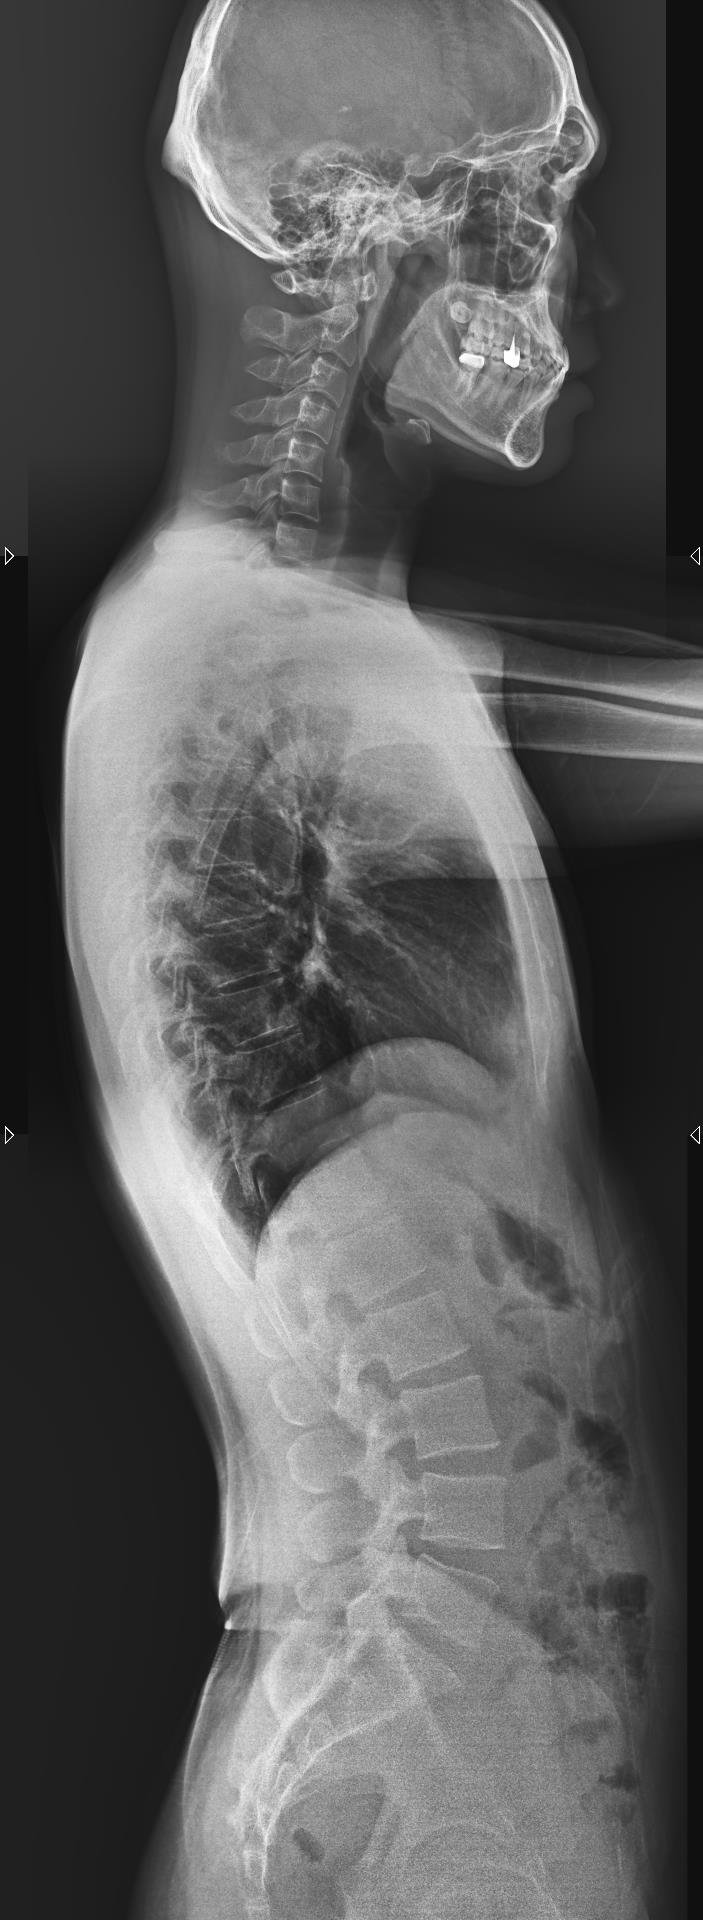

Ảnh chụp X-Quang cột sống (ảnh trên: một phần, ảnh dưới: toàn phần)